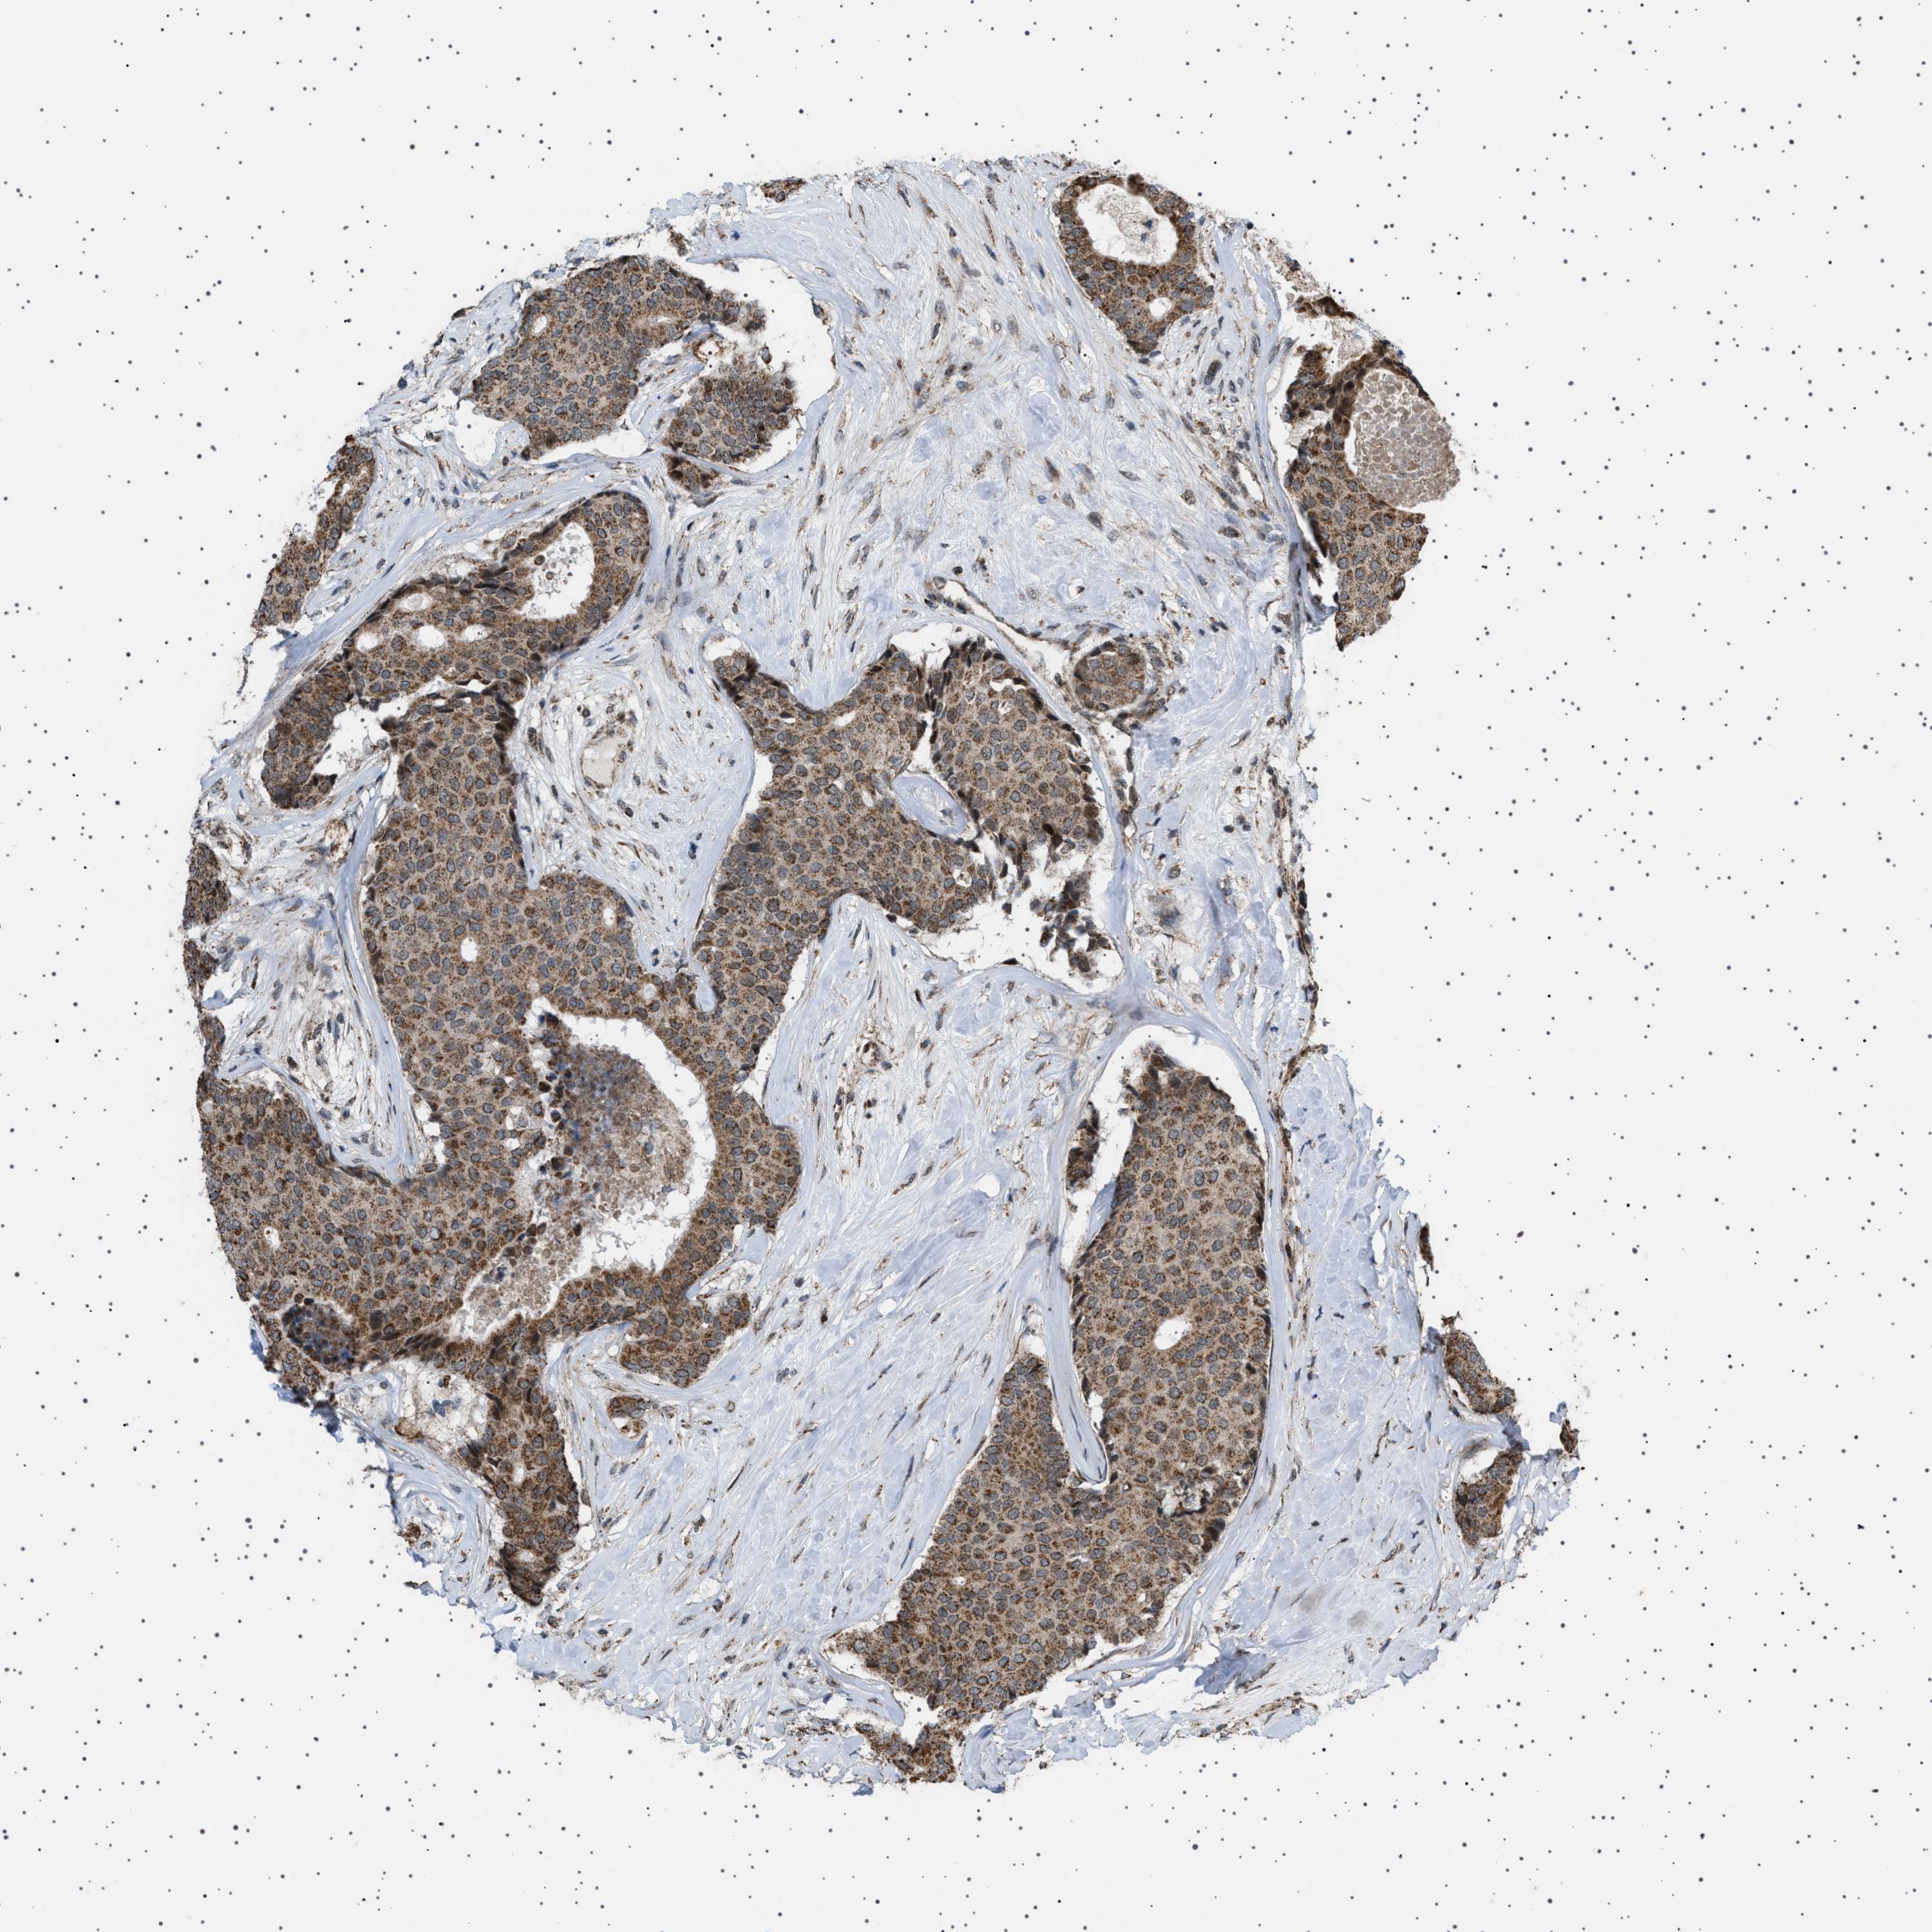

BRCA TCGA BRCA VALIDATION PROTEIN EXPRESSION

ANTIBODIES

AND

VALIDATION